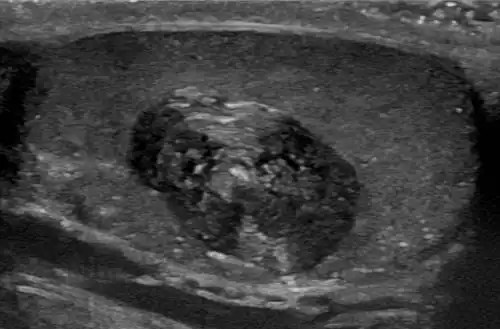

Epidermoid cyst in a testicle on ultrasound, with lamellated ("onion skin") appearance -